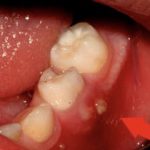

Ношение зубных протезов или брекетов неизбежно приводит к травмам слизистых оболочек. Врачи говорят, что несколько дней требуется для того, чтобы на месте использования конструкций сформировалась рубцовая ткань, которая будет их поддерживать. Если стараться полоскать рот Хлоргексидином или другими обеззараживающими средствами, заражения можно избежать. Несоблюдение рекомендаций, напротив, вызовет нагноение. Нужно насторожиться, если боль стала пульсирующей, а на десне появился прыщик с белой точкой внутри. Часто может повышаться температура, болеть голова.

На приеме врач производит осмотр, снимает зубной камень, под которым часто может скрываться источник проблемы. Слизистые оболочки чутко реагируют на любые заболевания зубов и десен. Причиной гнойного образования может быть стоматит, гингивит, пародонтит или даже кариес. Также на этом этапе важно снять отек, если он образовался и привел к флюсу. Если зуб мудрости не может прорезаться, карман иссекают, позволяя моляру выйти наружу. Брекеты и вставные челюсти корректируют, подгоняя по размеру.